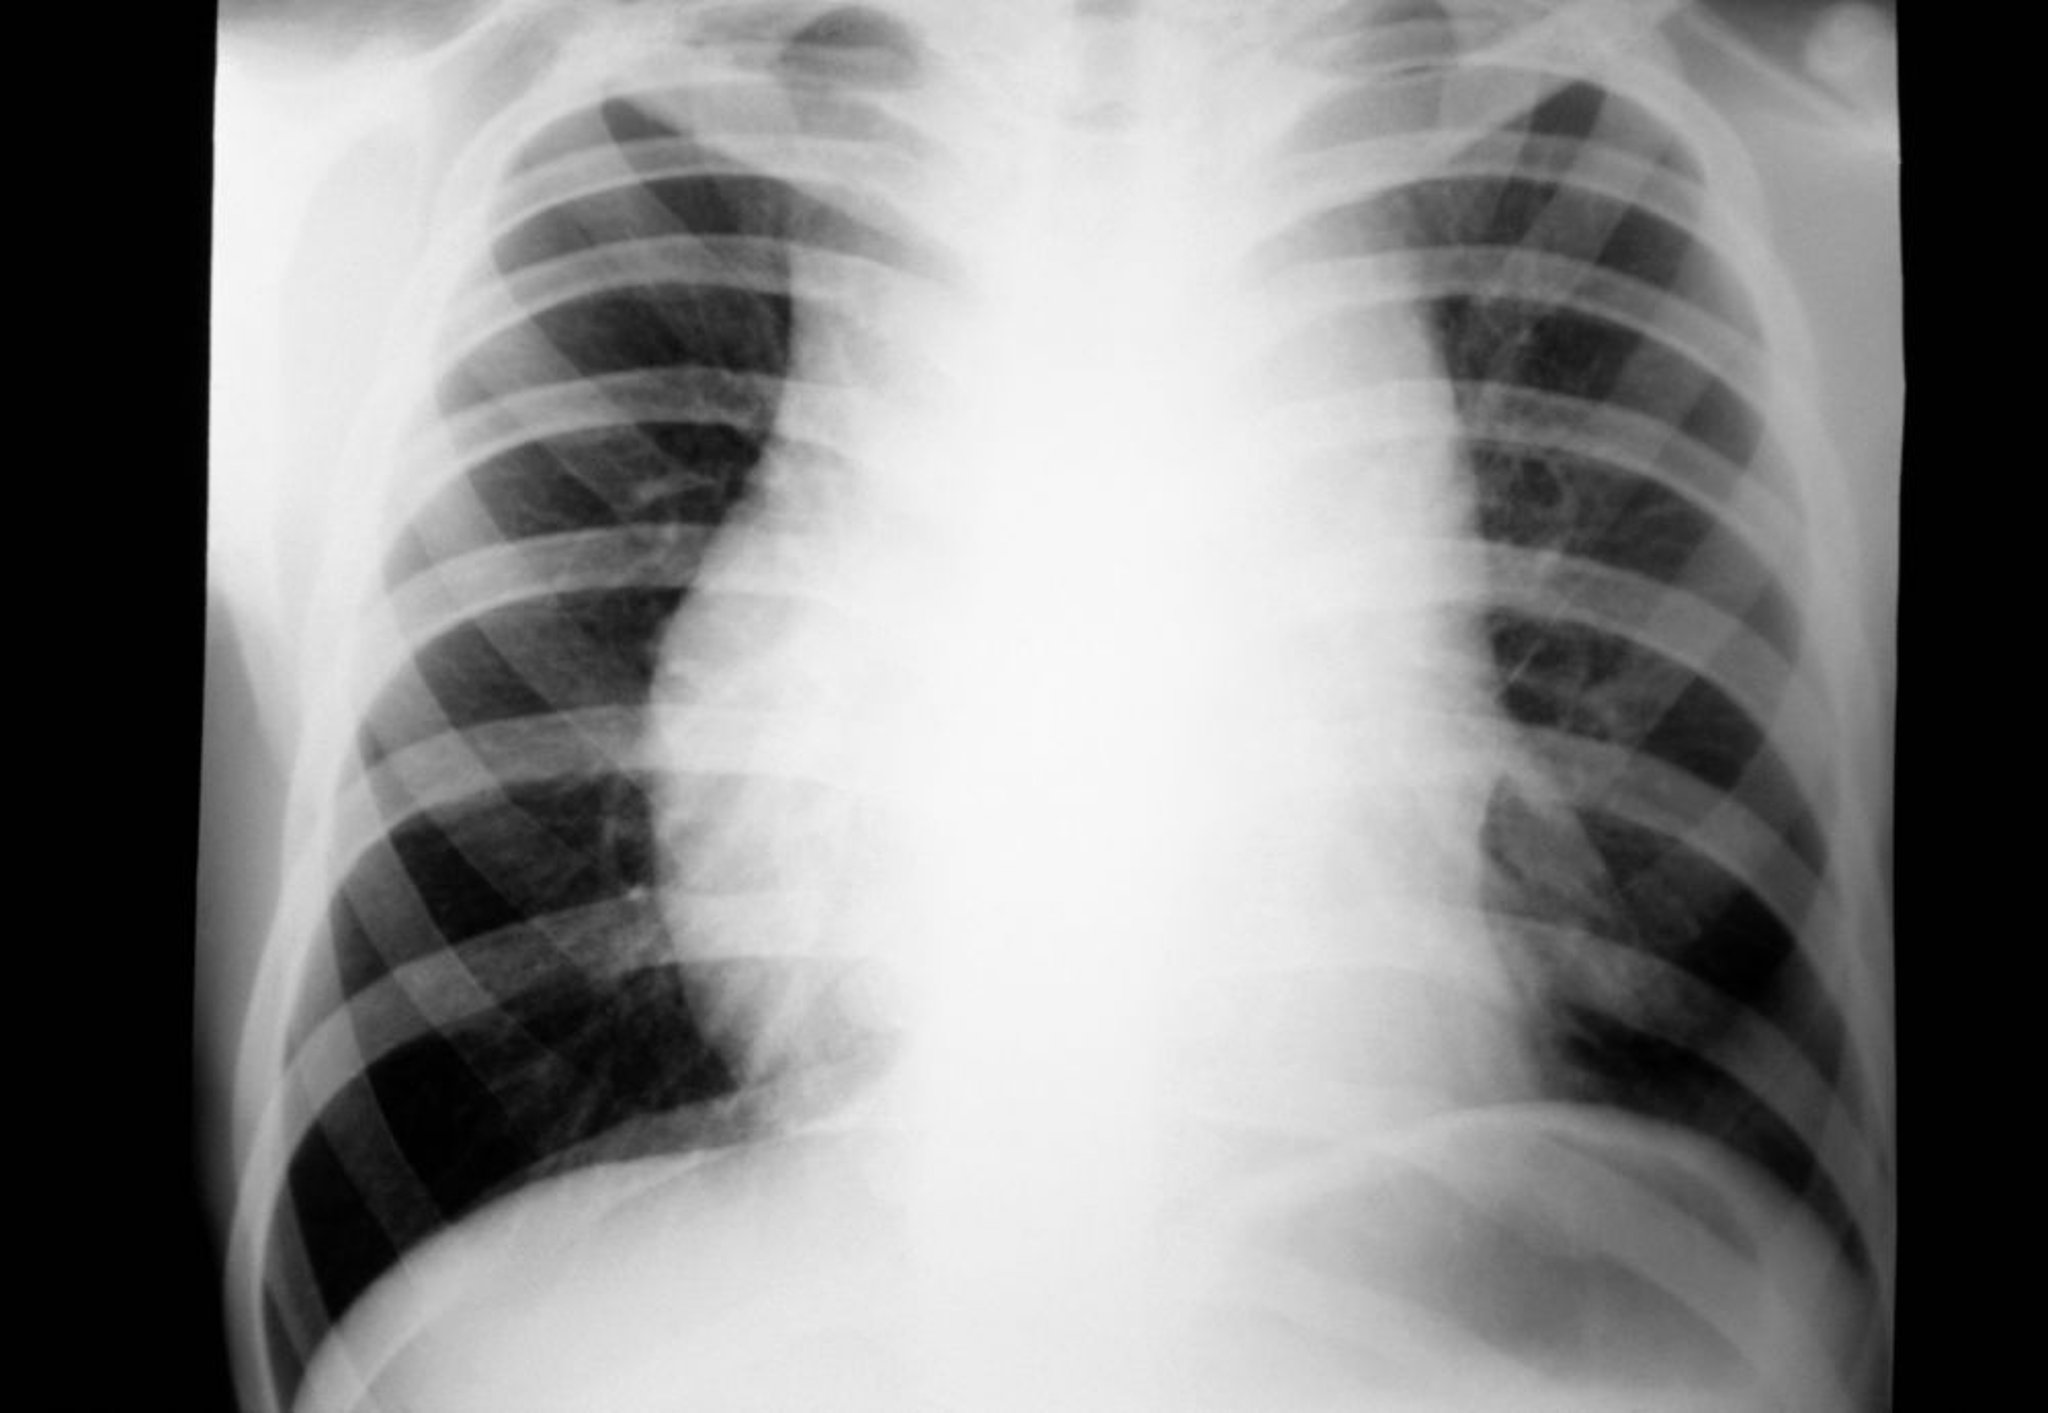

ホジキンリンパ腫(縦隔リンパ節腫脹)

縦隔リンパ節腫脹を示したホジキンリンパ腫患者の胸部X線写真である。